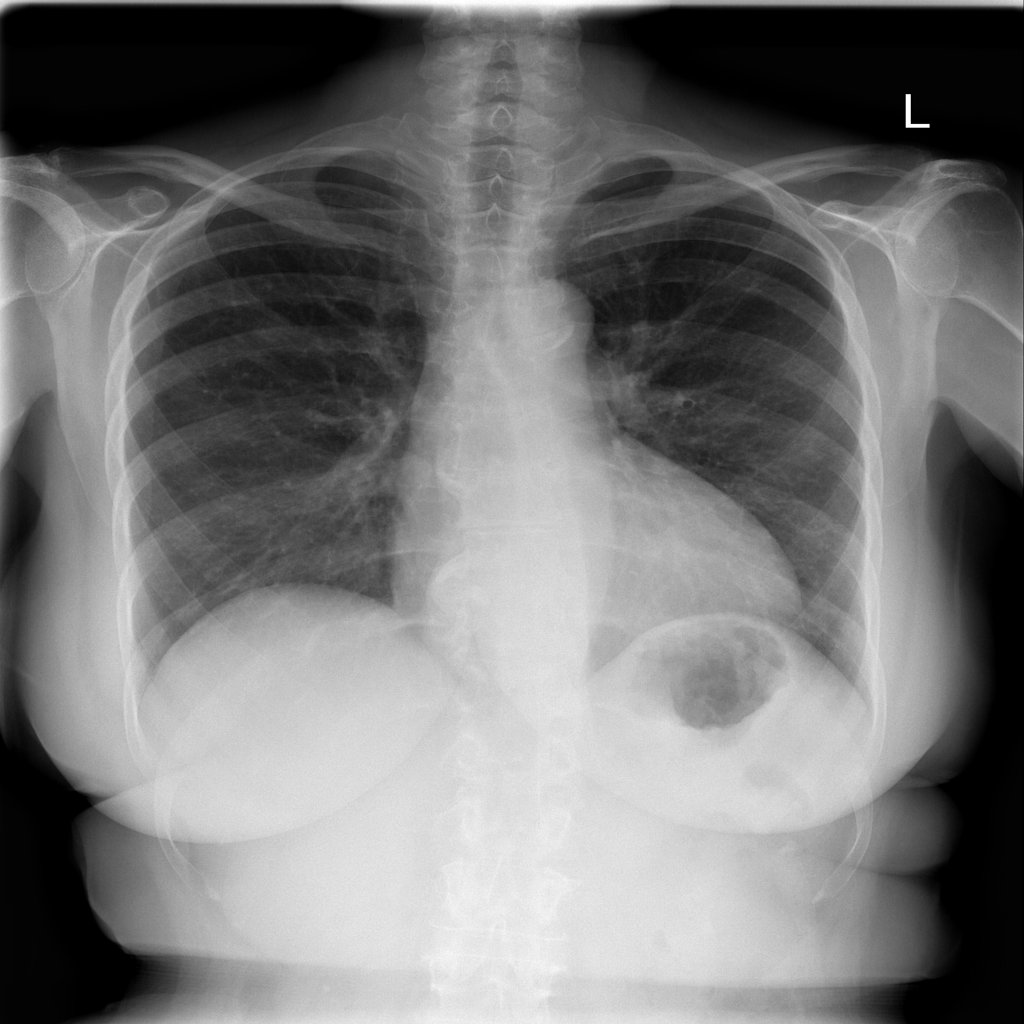

Cardiomegaly

Cardiomegaly means the heart appears enlarged on the chest X-ray. It is a descriptive imaging finding that can be related to heart strain, chronic pressure or volume changes, or even projection effects.

Showing up to 90 reference images for Cardiomegaly.

PAT-3384 · IMG-000Cardiomegaly

PAT-3384 · IMG-000

AP